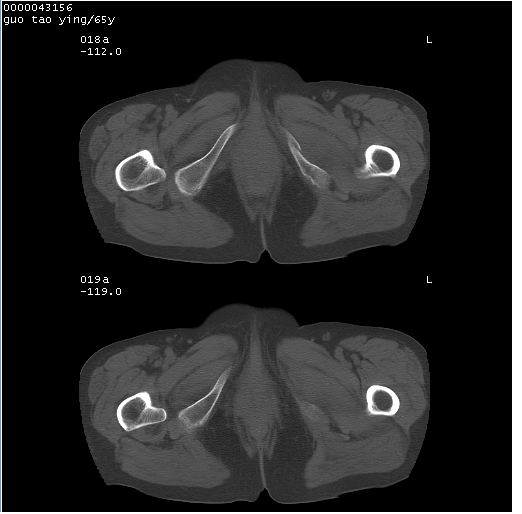

以下是引用黑白光影在2008-1-30 13:22:00的发言:[br]支持左耻骨骨折。[br]未见骶骨骨质明确破坏改变。[br]经楼主提示(勿局限于外伤)。考虑为右侧腹股沟直疝。[br][br][br][br]